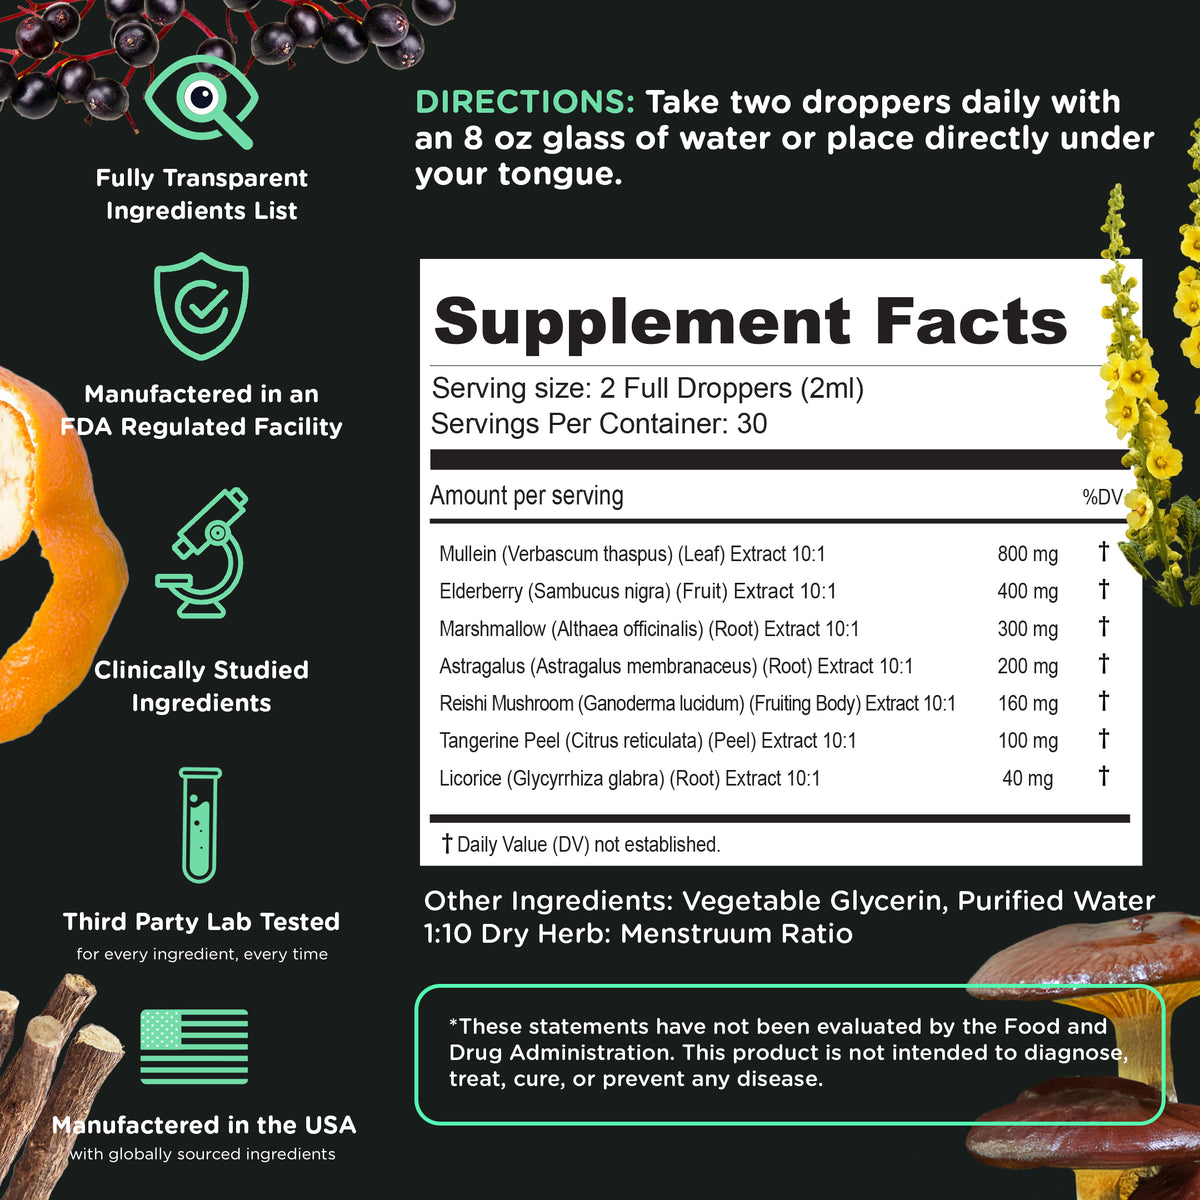

Take 2 full droppers (1 serving) every day directly under your tongue or mixed with your preferred beverage.

The ingredients in Super Lungs are 3rd-party tested prior to production for foreign microbials/pathogens (yeast, mold, Salmonella, E. coli, etc) heavy metals (arsenic, mercury, lead, cadmium etc) and are backed by gold-standard clinical trials/studies.

Take 2 full droppers (1 serving) every day directly under your tongue or mixed with your preferred beverage.

The ingredients in Super Lungs are 3rd-party tested prior to production for foreign microbials/pathogens (yeast, mold, Salmonella, E. coli, etc) heavy metals (arsenic, mercury, lead, cadmium etc) and are backed by gold-standard clinical trials/studies.

Take 2 full droppers daily, preferably with a meal.

Super Lungs is a concentrated liquid tincture of 7 extremely powerful herbs known for their lung/breathing boosting qualities.

We use a 10:1 extract ratio for maximum efficieny.

Super Lungs is made with premium ingredients selected for their protective and supportive properties. Each ingredient is carefully chosen and tested for quality.